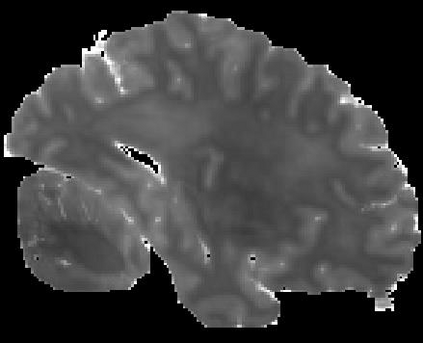

In neuroimaging, MRI tissue properties characterize underlying neurobiology, provide quantitative biomarkers for neurological disease detection and analysis, and can be used to synthesize arbitrary MRI contrasts. Estimating tissue properties from a single scan session using a protocol available on all clinical scanners promises to reduce scan time and cost, enable quantitative analysis in routine clinical scans and provide scan-independent biomarkers of disease. However, existing tissue properties estimation methods - most often $\mathbf{T_1}$ relaxation, $\mathbf{T_2^*}$ relaxation, and proton density ($\mathbf{PD}$) - require data from multiple scan sessions and cannot estimate all properties from a single clinically available MRI protocol such as the multiecho MRI scan. In addition, the widespread use of non-standard acquisition parameters across clinical imaging sites require estimation methods that can generalize across varying scanner parameters. However, existing learning methods are acquisition protocol specific and cannot estimate from heterogenous clinical data from different imaging sites. In this work we propose an unsupervised deep-learning strategy that employs MRI physics to estimate all three tissue properties from a single multiecho MRI scan session, and generalizes across varying acquisition parameters. The proposed strategy optimizes accurate synthesis of new MRI contrasts from estimated latent tissue properties, enabling unsupervised training, we also employ random acquisition parameters during training to achieve acquisition generalization. We provide the first demonstration of estimating all tissue properties from a single multiecho scan session. We demonstrate improved accuracy and generalizability for tissue property estimation and MRI synthesis.